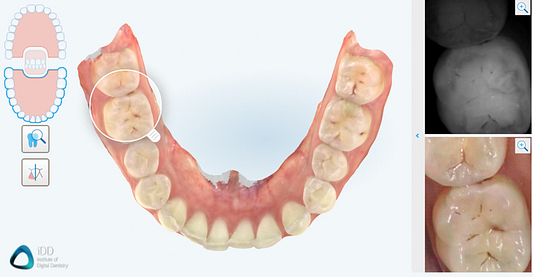

The iTero Element 5D Plus uses near-infrared imaging (NIRI) technology for caries detection, exactly the same as the Element 5D. This tech enables you to scan the internal structure of a tooth in real-time and functions as a diagnostic aid for the detection of interproximal carious lesions above the gingiva. You can also monitor the progress of such lesions without the need for radiography. It is an excellent and innovative piece of technology that works well. iTero is the first to use NIRI technology in an intraoral scanner, and it is arguably the best caries detection tool in any scanner available on the market. The iTero Element 5D Plus is also the only scanner (besides the Element 5D) that simultaneously records 3D scans, intraoral 2D color images, and NIRI images in one scan. The only other scanners with caries detection functions are the TRIOS4 and Planmeca Emerald S, but these require additional scans to be taken.

The iTero Element 5D Plus enables the comparison of these images over time using the iTero TimeLapse function, which is a neat feature and great for patient education and communication. Although not unique to iTero, the TimeLapse feature enables comparing different scans that have been taken at different times. This allows you to predict issues and diagnose problems by comparing any changes in these scans over time. An example of this feature would be reviewing soft tissue recession, abrasion, erosion, and tooth movement. The comprehensive imaging system seen in the iTero Element 5D Plus gives clinicians an excellent reason to incorporate the iTero in every patient examination, at every visit. Rather than just an impression tool, this changes the whole dynamic of an intraoral scanner as it can also help with diagnostics. NIRI technology may be heralding a new era of patient management and education.

The one thing to note is that the NIRI images require training and a good understanding of what you are examining with this technology. It can sometimes be tricky to tell what it is showing and whether it is just normal anatomy. Like with any diagnostic tool, you obviously wouldn't rely on this to make clinical judgments, and it is designed to compliment all other diagnostic tools you may use. Overall, a great feature that is nice to see in an intraoral scanner. It has many uses, for example, screening a pregnant patient or those who refuse radiography for whatever reason.

NIRI a useful caries detection aid built into the iTero Element 5D and 5D Plus